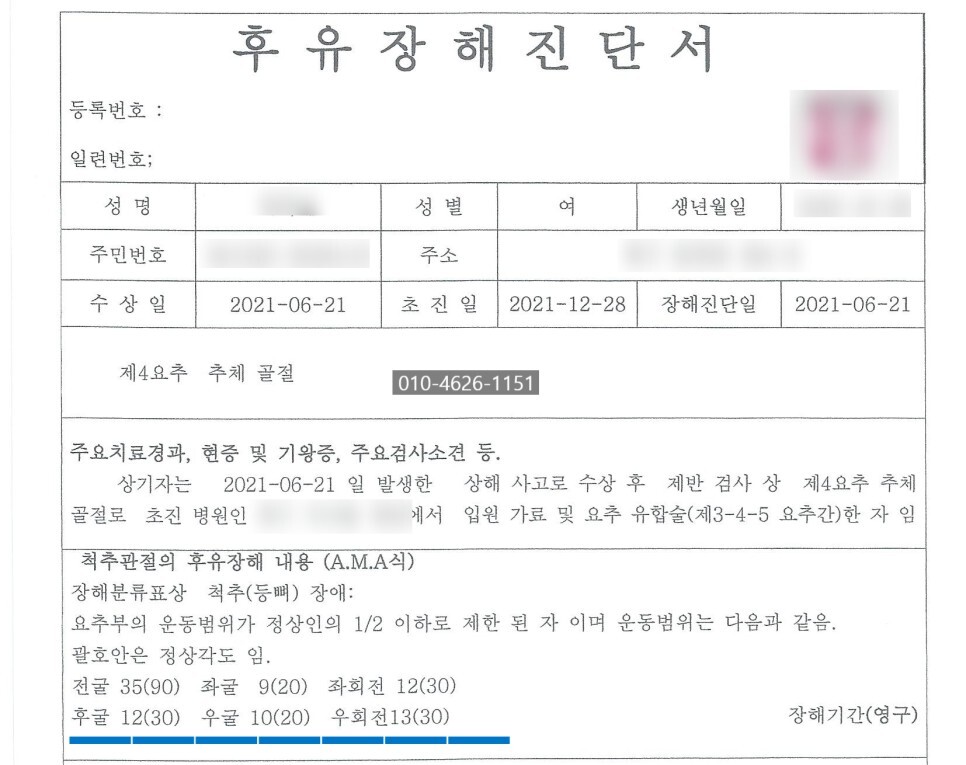

사고 이후 6개월 경과 후 후유장해

진단 위해 병원 내원하였고,

'척추의 뚜렷한 운동장해(장해율 30%)'

'척추의 중도의 운동장해(장해4급)'

후유장해진단서 발급 하였습니다.